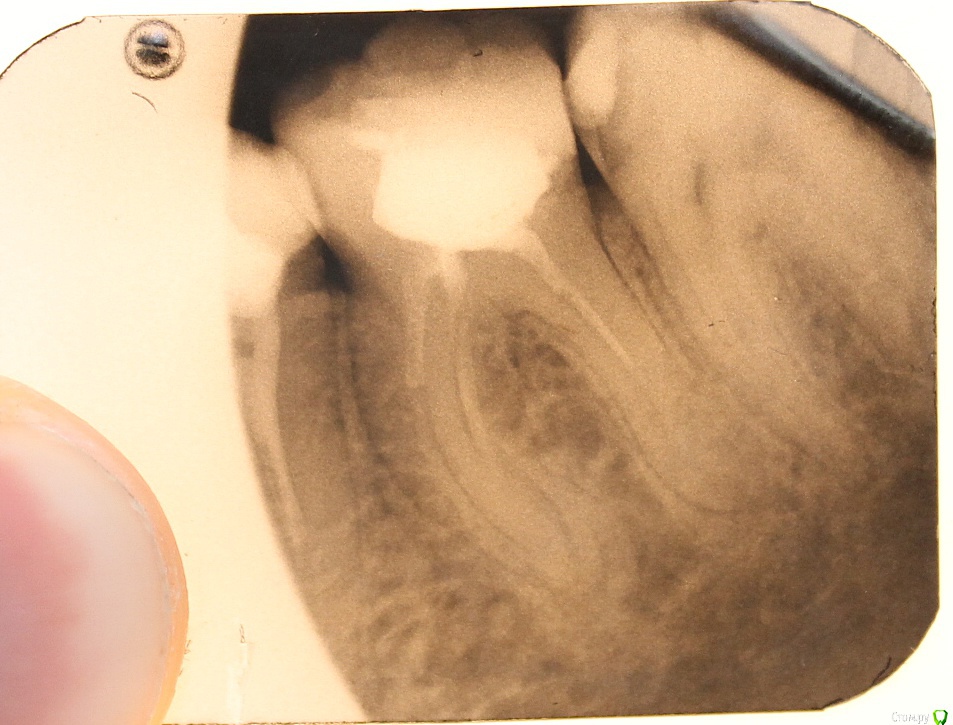

ARislanV Опубликовано 28 мая, 2015 Поделиться Опубликовано 28 мая, 2015 Приветствую всех, Здравствуйте, Начинаем!Пол года назад лечил 36Pt зуб, коронковая часть разрушена на 70 %, восстановил все композитом с перекрытием бугров.Сейчас зуб треснул, по словам удалявшего хирурга трещина до бифуркации. Почему он раскололся? Ведь что интересно, трещина прошла не по краю зуб/пломба ( в самом слабом месте), а посередине пломбы т.е. пломба разорвалась по палам. А какая сила должна была быть, что бы разорвать пломбу по полам?) И следующий вопрос, что делать и как делать, чтобы такого не было? ( потому что мне было очень не приятно видеть такое со своей работой) Ссылка на комментарий

ARislanV Опубликовано 28 мая, 2015 Автор Поделиться Опубликовано 28 мая, 2015 Я такие зубы когда пац не хочет протезироват, делаю запис в карте что рекомендовано тота тота с последствиями ознакомлен и т.п. Половина зуба заливаю жидким композитом а потом пакуемым вост сверху но стенки зуба укоротив по высоте и это укорочение компенсирую пакуемым. Типа как внутри полости пломба с переходом на края стенок. Пломба ввиде грибка. Палюбому ел кашу))Мой зуб был восстановлен именно таким способом, как вы описываете( в виде гриба)Но какова должна была быть сила, что бы разорвать пломбу пополам? Ссылка на комментарий

M@estro Опубликовано 28 мая, 2015 Поделиться Опубликовано 28 мая, 2015 Этот зуб был разрушен на 70%, конечно его нельзя было восстанавливать пломбой.) Это моя ошибка, из за которой доверие пац ко мне сильно снизилось. Но я не могу понять, при каких случаях надо: - Делать вкладку и коронку- Пломбу и коронку- Вкладку керамическую Объясните пожалуйста?) пломба - 30 процентов разрушения по площади, витальный зуб. Полость мод , отсутие хотя бы двух стенок - вкладка . Депульпированный зуб . если отсутсвует две стенки и площадь разрушения не более 50 % ( первичный пульпит МОЛЯРА ) - вкладка / накладка. С премолярами сложнее , если стенки более 1.5 мм толщиной - можно сделать коронку 3/4 , в остальных случаях - коронка. Если имеем мод полость у моляра, и зуб депульпирован - то это коронка. Ссылка на комментарий